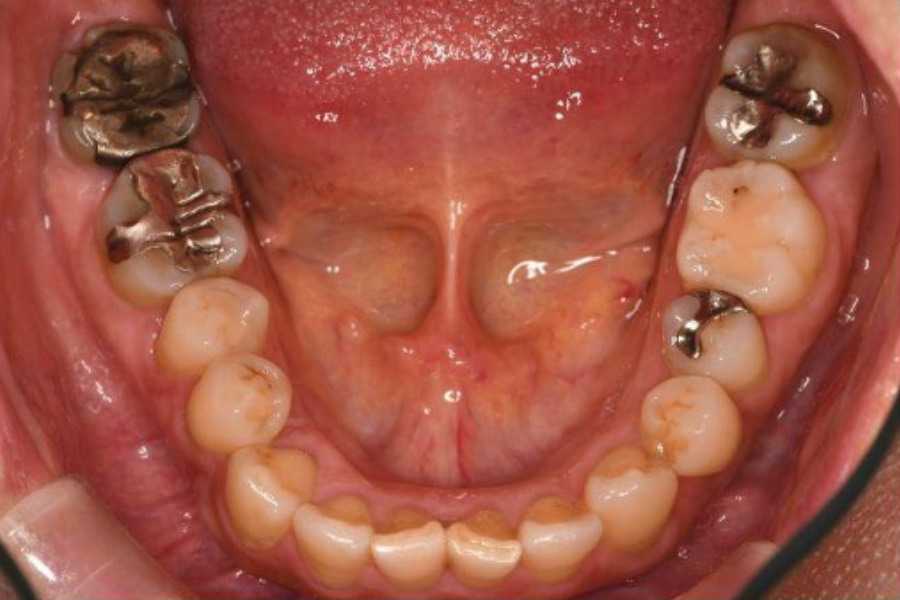

治療前

| 治療内容 | 全顎治療:歯周病治療、根管治療、 歯肉弁剥離掻爬術(フラップ手術)、 セラミック治療、ダイレクトボンディング |